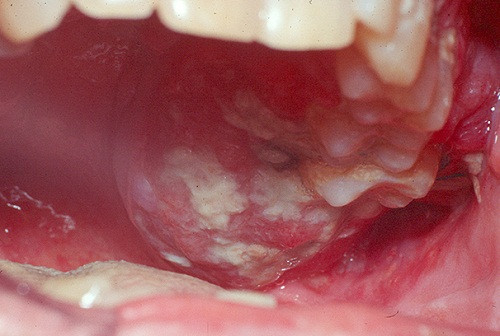

Một trong những triệu chứng thường thấy của ung thư môi là việc xuất hiện các vết loét khó lành, thường ở dạng cục mảng trắng trên môi hoặc vị trí quanh miệng, dễ gây cảm giác đau đớn. Ảnh: vienyhocungdung.

Nếu bạn bị những triệu chứng trên kéo dài hơn 2 tuần không khỏi dù đã sử dụng thuốc và các biện pháp điều trị khác thì có thể đây là dấu hiệu cảnh báo bệnh ung thư. Ảnh: benhvienk.